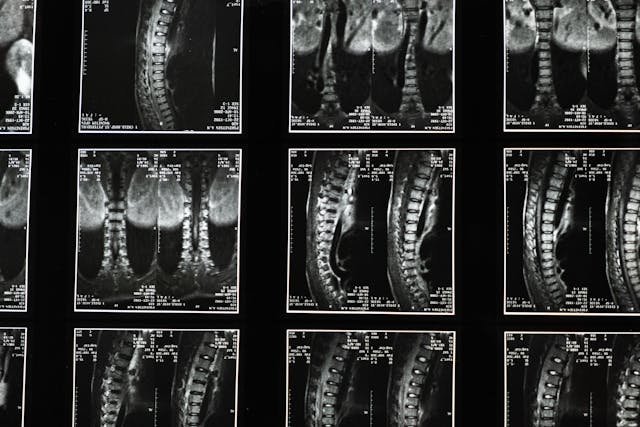

Types of Spine Surgery

Different forms of spine surgery may offer relief when non-surgical therapies are ineffective. A discectomy releases pressure on the nerves by removing a portion of a herniated disc. By removing the lamina, a portion of the vertebral bone, laminectomy relieves pressure on the spinal cord and surrounding nerves. A common treatment for disorders like degenerative disc disease is spinal fusion, which joins two or more vertebrae to stabilize the spine. There are distinct benefits, dangers, and indications for every surgery. While they may not require as much recovery time, discectomy and laminectomy can swiftly ease pain. Long-term stability is provided via spinal fusion, but recovery time is increased. Being aware of these processes enables you to choose your course of treatment with knowledge. To get the best potential outcome, discuss with your surgeon the appropriate course of action for your disease.